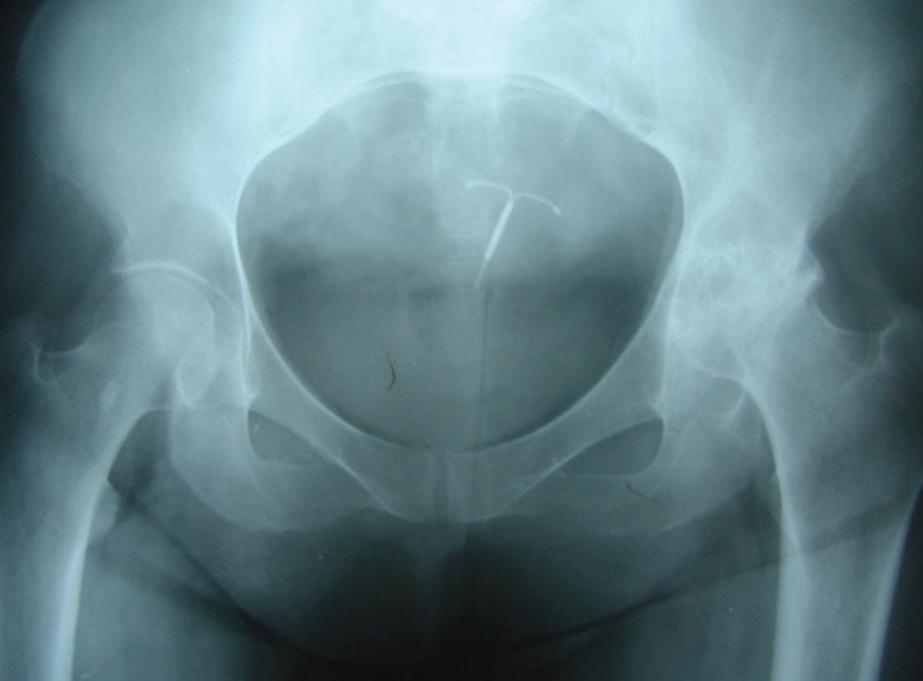

Kalça kireçlenmesi bulguları olan bir hastada yürüyüşünden tanı koymak mümkündür. Hastanın öyküsü dinlendikten sonra fiziksel muayenesi yapılır. Eklem aralığında daralma, yeni kemik oluşumu, kalça kırık ve çıkıklarının teşhisi için röntgen filmi çekilir. Kalça kireçlenmesinin birinci tanı yöntemi röntgendir.

Sol kalçasında artroz olan hastanın röntgen filmi